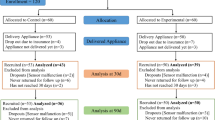

Eleven females and 19 males were recruited from two dental practices before treatment with an oral appliance and enrolled in the study. Twenty-five of the patients had failed CPAP therapy. After obtaining an informed consent (approved by the BioMed IRB, San Diego, CA, USA) patients completed a two-night pretreatment in-home study with the Apnea Risk Evaluation System (ARES TM) Unicorder TM (Advanced Brain Monitoring, Carlsbad, CA, USA). This pretreatment recording was conducted between the time the dental impressions were taken and when the TAP II Mandibular Advancement Device (MAD) (Airway Management, Dallas, TX, USA) was fabricated and ready for insertion.

On the day of insertion of the MAD, patients completed the Beck depression index, Epworth sleepiness scale, and the Flemons’ quality of life questionnaire. At the insertion appointment, both study sites attempted to achieve a starting MAD titration position whereby the patient could just hook the lower tray with the upper tray using active protrusion with both trays in place. In the rare occasion that this level of advancement was not tolerated by the patient, the starting protrusion was reduced. Patients were instructed to begin adjusting the MAD in one-half turn increments as soon as it was tolerable, until a cessation in snoring or the symptoms had resolved. As a result, the titration endpoint was determined by the dentist based on the patient’s self-report. At the follow-up appointment, which was typically scheduled 3 to 4 weeks subsequent to the MAD insertion, the assessment questionnaires were completed again and the ARES Unicorder study was repeated. Twenty-seven of the 30 patients reached their endpoint within 34 days. The other three patients completed their endpoint in 40, 61, and 75 days; the delay in reaching the endpoint was due to patient illness unrelated to this study.

To identify anthropomorphic factors that may impact MAD treatment outcomes, patients were stratified into two groups. Group 1 included all patients with a posttreatment AHI-4% ≤ 5 (n = 18). The balance of patients with an AHI-4% > 5 were assigned to group 2 (n = 12). Paired t tests were used to identify significant group differences.

To develop and validate the prediction of the posttreatment AHI using pretreatment data, patients were paired and assigned into either the model development or cross validation group based on similarities in the pre- and post-4% AHI and 1% AHI. Correlation analysis was used to identify anthropomorphic variables and measures of obstructive breathing before treatment which might be useful in estimating the posttreatment 4% AHI (post-T 4%). Variables with significant correlations were then used in a linear regression to derive predicted posttreatment values (predict AHI).